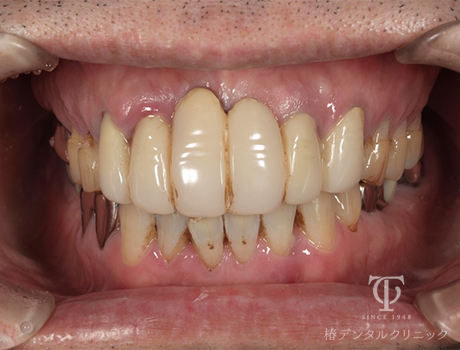

Case04

術前

-

術後の上顎内冠

術後の上顎AGCテレスコープ義歯

正面観AGCテレスコープ義歯装着

- 症状

- 右上の痛み

- 治療期間

- 約1年半

- 治療費用

- (上顎)インプラント治療:473,000円×2

(上顎)AGCテレスコープ義歯:1,500,000円

(下顎)インプラント治療:473,000円×2

右上の歯が痛いということで来院されました。インプラントとAGCテレスコープという方法でかみ合わせを再構築しました。

【リスク・副作用】

インプラント治療後、痛みや違和感、出血、腫れなどが出る事があります。喫煙者、糖尿病などの方の場合、歯が生着しない場合があります。入れ歯を清潔に保たないと虫歯や歯肉炎、歯周病になるリスクがあります。